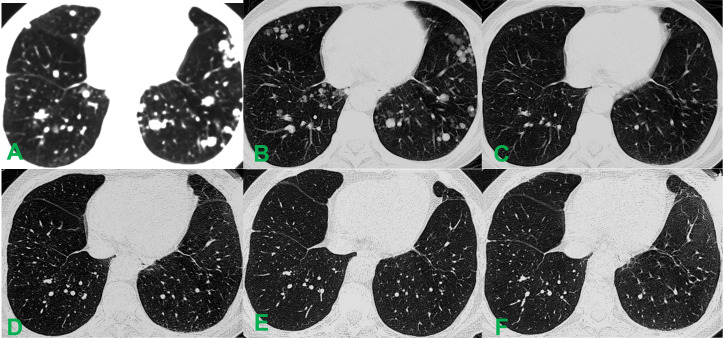

诊断评估:影像学检查显示肿瘤位于肝第Ⅶ、Ⅷ段,大小约14×12×10 cm。甲胎蛋白(AFP)为2107 ng/ml,右支肝静脉内可见HVTT。双肺可见多发弥漫性结节。BCLC分期为C期。肝脏穿刺病理活检确诊为HCC(图1,图2)。

图2. 术前术后胸部CT影像对比。(A)术前肺部CT显示双肺弥漫性转移灶(>20个),最大病灶直径约1.5 cm。(B)术后4周,肺部转移灶的数量和体积均减少,最大结节直径约1.0 cm。(C)术后12周,弥漫性转移结节完全消失。(D)术后3年随访平扫CT未见新发病灶。(E)术后5年肺部CT显示病情持续缓解。(F)术后10年随访CT示影像学稳定,无新发或复发。

治疗后第4天和第7天AFP、白蛋白(ALB)、丙氨酸氨基转移酶(ALT)、天冬氨酸氨基转移酶(AST)和总胆红素(TBIL)水平的连续变化见表1。治疗4周后增强CT示病灶呈弥漫低密度,肺内多发粟粒样转移结节轻度缩小(图1C,图2B)。至第12周,肝脏肿瘤完全坏死、体积缩小约80%,肺转移灶基本消退(图1D,图2C)。后续影像证实肺转移灶完全消失,肝内病灶及瘤栓逐渐消退,最终达完全缓解。